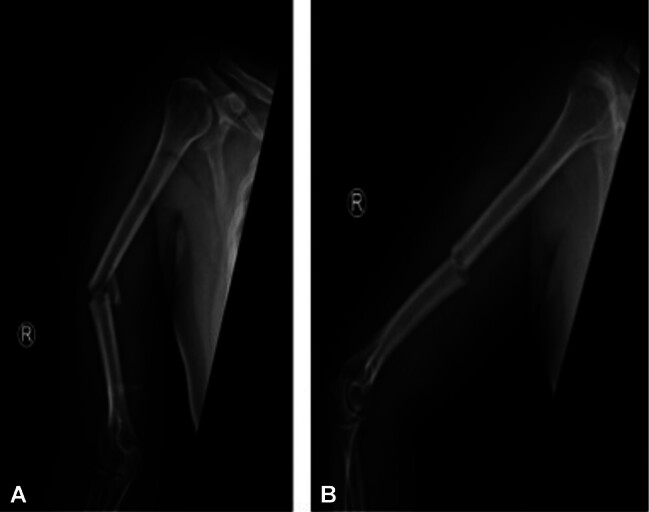

Abstract Image